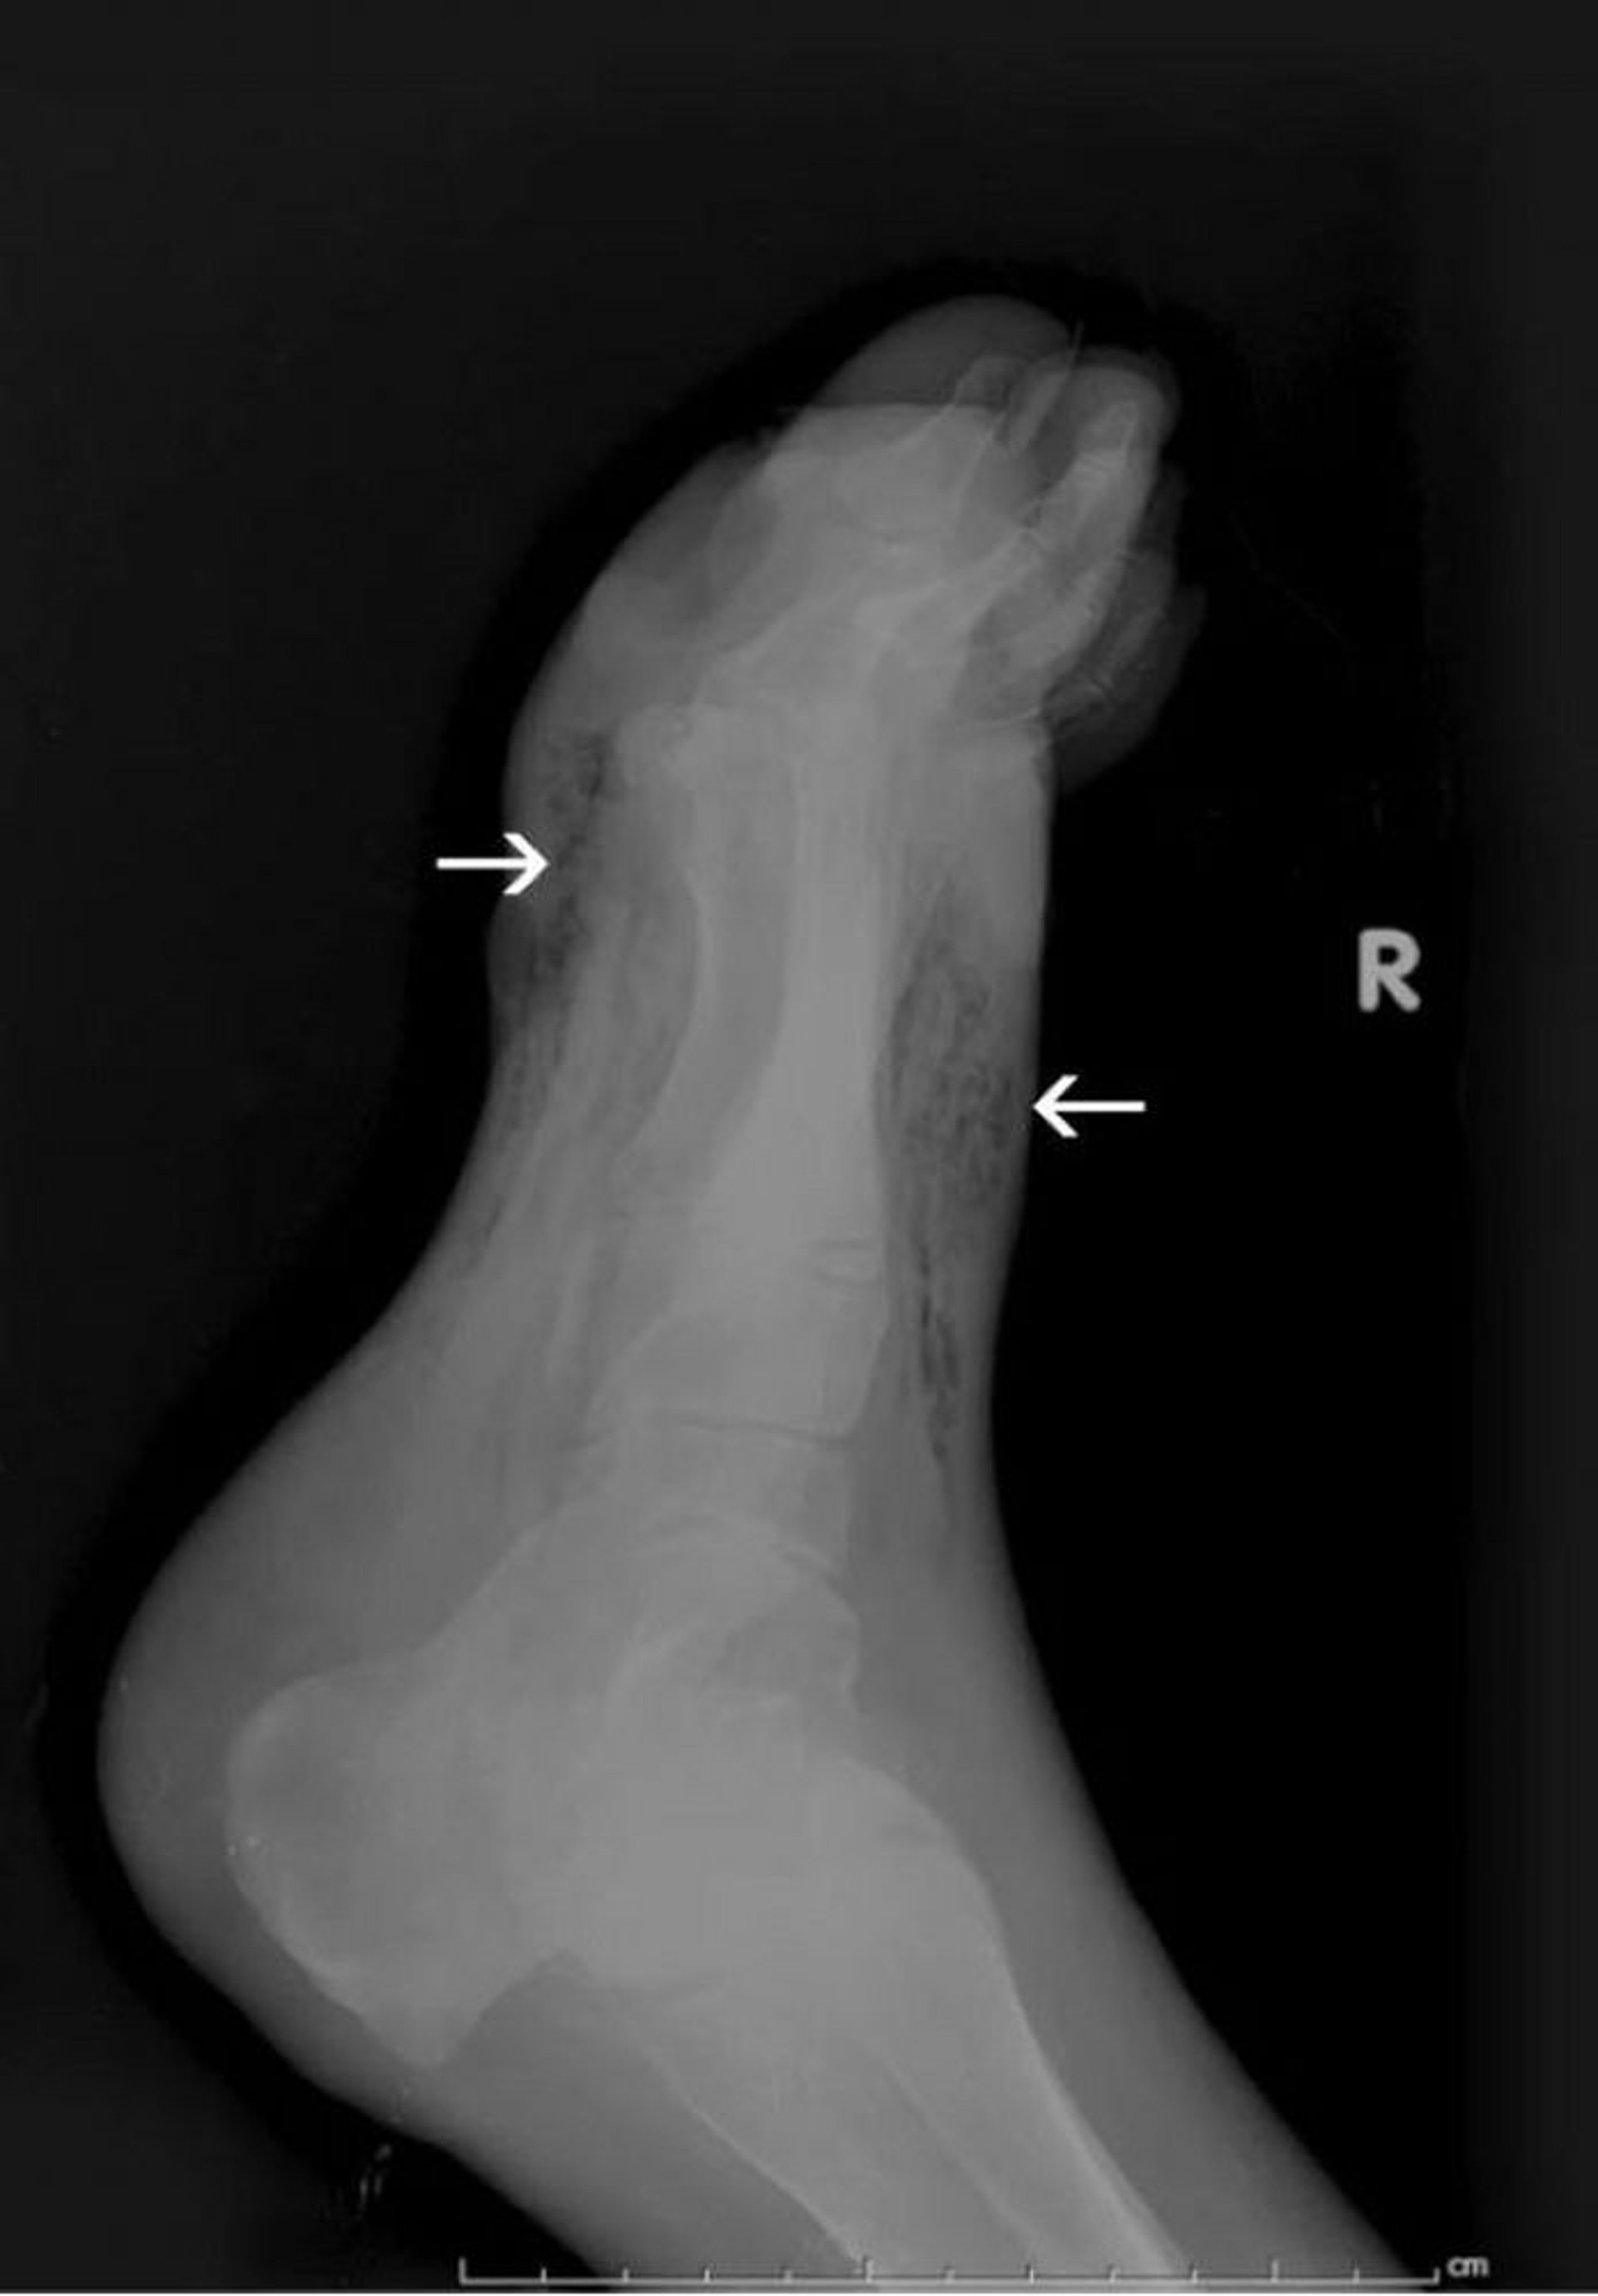

Gangrène du pied (radiographie)

Cette radiographie montre des gaz dans les tissus mous du pied (flèches).